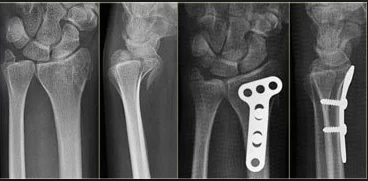

Colle’s Fracture

- Extra-articular fracture of the distal radius with dorsal and radial displacement of the wrist “Dinner fork” deformity

- Seen in elderly with osteoporosis

- Caused by falling on the outstretched hand

Treatment

- Undisplaced : Cast alone

- Displaced: (Sedation/ UGA / ULA), closed reduction, casting Wrist immobilized in flexion & ulnar deviation

Intra-articular Distal Radius Fracture

- treated by anatomical open reduction, internal fixation and early mobilization